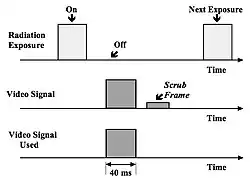

Pulsed progressive readout (PPR) of the video camera target can be used to minimise persistence effects. Here the conventional interlaced scanning of the target is replaced by a progressive scan where each video line is read sequentially. The sequence of events, see Figure 6.19, is as follows:

- First, the exposure pulse is produced and the image accumulates on the target of the video camera. The target is blanked during this period, i.e. it is not scanned by the electron beam.

- Next, the target is scanned in a progressive fashion in a standard frame period and most of the image information is read off. This image information is fed to the digital image processor for subsequent processing.

- Finally, the target is read again in order to discharge the target of any residual image signals (lag) and to prepare the target for the next image. This latter scan is commonly referred to as a Scrub Frame.

The PPR mode of operation is also used because it allows video scanning to occur with independence from the duration of the radiation exposure. Such independence allows the application of exposure pulses of variable length - which gives some flexibility in the design of X-ray generators.

Independence from image persistence effects allows the utilisation of the information from virtually all of the radiation exposure without any contributions from image build-up and decay effects. In addition, images of better spatial resolution have been obtained using the PPR mode. A disadvantage of the approach however is that, since two video frame periods are required for each image, the maximum frame rate for PPR exposures is about half that of continuous interlaced raster scanning.